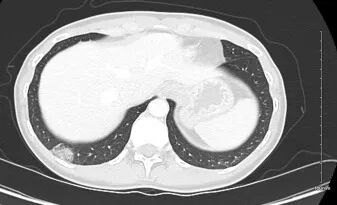

腹部和盆腔CT扫描(静脉注射对比剂)显示患者左侧有一颗3-4毫米的输尿管结石

,伴有轻度肾积水;右下叶后基底段有一个2.4厘米的亚实性肺结节

,内含致密磨玻璃及部分实性衰减成分,所见其余肺野无异常发现(图1)。泌尿科医生在患者初次就诊后6周后安排的随访CT成像中,2.4厘米的亚实性肺结节持续存在,其大小及实性成分(测量至少8毫米)均未见明显变化(图2)。患者被转诊至肺结节门诊。

图1. 腹部盆腔增强CT扫描显示一个2.4厘米的亚实性肺结节,内含致密磨玻璃及部分实性衰减成分。图像以肺窗显示,层厚2.5毫米。